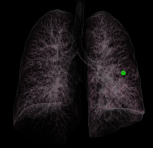

Chẩn đoán hình ảnh mô mềm tiên tiến cho vùng bụng.

Tăng cường độ tương phản I-ốt.

Hỗ trợ đánh giá an toàn cho bệnh nhân.

Đảm bảo hình ảnh chất lượng cao.